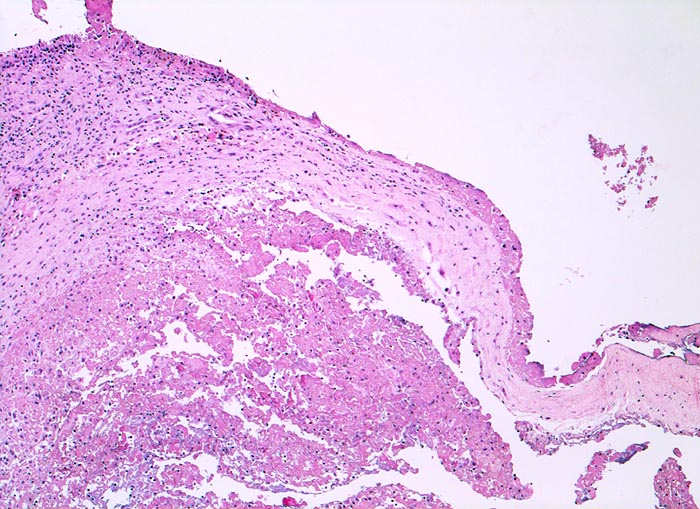

fibrinöse Synovialitis bei chronischer Polyarthritis

Synovialis

Anstelle der synovialen Deckzellschicht sind die Zotten der Synovialis von einer dicken Fibrinschicht durchmischt mit Granulozyten bedeckt.

Bekannte seropositive chronische Polyarthritis.

Eine akute fibrinöse Entzündung findet sich häufig bei einer floriden chronischen Polyarthritis.

Histologie

50